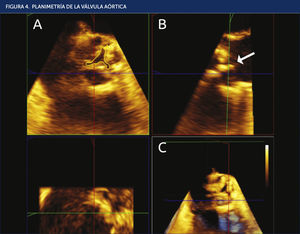

NUEVAS HERRAMIENTAS PARA ESTIMACIÓN DE SEVERIDADEcocardiograma 3D:La tecnología 3D permite obtener pirámides de datos en sectores de exploración de 30° í 60°. Estas pirámides incluyen abundante información desde la raíz de la aorta hasta el TSVI, incluyendo las sigmoideas aórticas. El posprocesado y la reconstrucción multiplanar permiten estudiar la válvula en cualquier plano y ángulo, de manera que se obtienen resultados satisfactorios en un porcentaje muy elevado de pacientes. Para la medición del área de apertura valvular aórtica se deben obtener imágenes en tiempo real (Live 3D). A fin de obtener una frecuencia de adquisición superior a 20Hz, se deben reducir el ángulo y la profundidad del sector de exploración. El posprocesado de las imágenes permite la reconstrucción de cualquier plano del volumen piramidal obtenido previamente para obtener el área de apertura valvular a nivel de las cúspides valvulares (Figura 4).

PLANIMETRÍA DE LA VÁLVULA AÓRTICA

Planimetría del orifi de apertura valvular aórtico mediante el sistema de reconstrucción multiplanar (MPR). Tras seleccionar la imagen de máxima apertura valvular en la imagen 3D (C), se obtienen los planos longitudinal (B) y transversal (A) de la válvula. El plano de corte transversal (en verde) se ajusta para que pase por el borde de las cúspides (fl modifi su inclinación en caso necesario para obtener la imagen más parecida a la tridimensional. Posteriormente, se amplía la imagen para realizar la planimetría de forma manual.

Cuando se compara esta metodología con la ecuación de continuidad, se observa una infraestimación ligera del área de apertura valvular, en torno a 0,04 cm2 (IC 95%: 0,530 • 0,839)11. En general, el área anatómica debería ser superior al área efectiva12. Posiblemente, una menor resolución espacial de la ETE 3D sea la razón de estas discrepancias. El coeficiente de correlación interobservadores, de 0,871 (0,780•0,925), indica una buena reproducibilidad de las medidas.